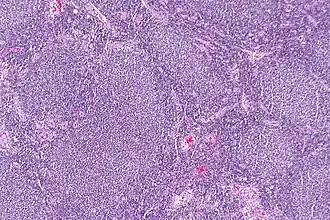

| Linfonodo com linfoma folicular com a formação de "folículos" que lhe é característica. | |

Linfoma folicular, linfoma centrolástico, linfoma nodular ou doença de Brill-Symmers[1] é um tipo de câncer que se origina nos linfócitos B nos folículos dos linfonodos e representa cerca de 20 a 30% dos Linfoma não Hodgkin.